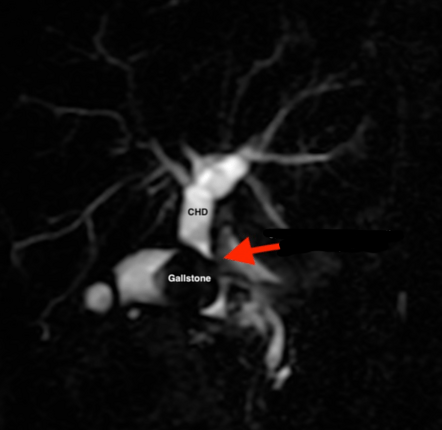

What is Mirizzi's syndrome?